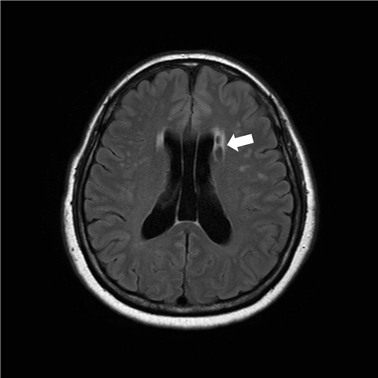

뇌경색 초기증상으로 복시를 예로 들수 있다는데요 후두엽의 혈관이 막히면 시력 저하나 복시가 보여집니다니다. 또한 단순히 시력 상실이라기보다는 텍스트나 사물이 겹쳐 잘 보이지 않는 증상이예요.그래서 보통 시력이 점점 감량하게 되었는존재하는데 뇌경색의 경우 가파르게 시력이 떨어한 경우 혹은 한쪽 눈이 안 보이게 되는 추세가 있습니다.

뇌경색 초기증상 7 안면 근육 마비

안면 신경을 관장하는 뇌혈관이 막힐 경우 입이 삐뚤어지는 증상과 안면 근육이 틀어지거나 마비되는 증상이 발생할 수 있다고 합니다. 안면마비의 경우 뇌경색이 전대 뇌동맥에 발생하여 일어나는 되었다면로제일 일반적으로 일어나는 증상이예요. 이이것만이 아니라 하체 쪽에도 마비 증상이 찾아오거나 감각 상실과 같은 증상이 나타날수 있습니다.